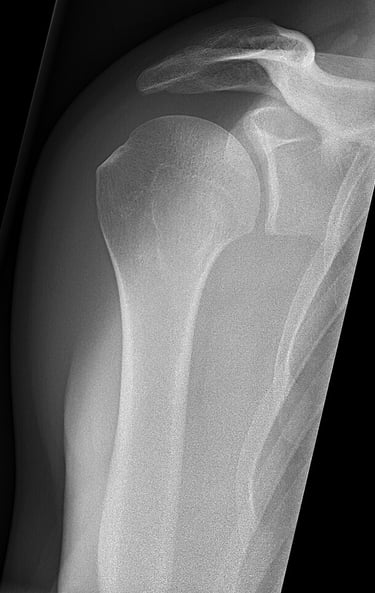

La inestabilidad de hombro aparece cuando la cabeza del húmero se desplaza parcial o totalmente fuera de su posición normal en la cavidad glenoidea de la escápula. Esta pérdida de congruencia durante el movimento puede deberse a una luxación previa, microtraumatismos repetidos o una laxitud articular generalizada.

La articulación del hombro está formada por la cabeza del húmero -que es esférica- y la cavidad glenoidea de la escápula -que es más pequeña y plana-, similar a una pelota de golf sobre su base. Esto otorga una gran movilidad al complejo del hombro en diferentes planos, pero le resta estabilidad a la hora de controlar ese movimiento.

Para reforzar esa estabilidad tenemos elementos activos: músculos y tendones, y elementos pasivos: ligamentos, cápsula y rodete articular del labrum. El fallo de alguno de estos elementos puede dar lugar a un hombro inestable.